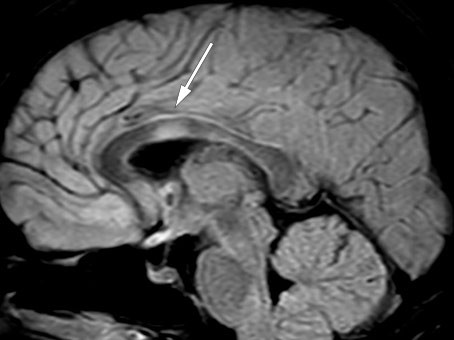

Kontroll-MR en måned senere viste tilkommet lesjon i høyre thalamus uten kontrastoppladning (figur 2) samt to nye, små lesjoner med kontrastladning i medulla ved C5, C6 og muligens også Th5. De infratentorielle lesjonene hadde gått fullstendig tilbake, og forandringene i medulla oblongata var redusert.

Akutt disseminert encefalomyelitt er oftest monofasisk og behandles vanligvis med steroider i fire til seks uker. Dynamikken i MR-bildene kunne derfor tale både for revurdering av diagnosen og for ytterligere antiinflammatorisk behandling. Pasienten rapporterte imidlertid om god klinisk form, og prøver for ACE, nevronale antistoffer, encefalittantistoffer, akvaporin-4-antistoffer og MOG-antistoffer samt cytologiske prøver av cerebrospinalvæsken var negative. Man valgte derfor å avvente ytterligere behandling, og pasienten ble søkt til rehabilitering for vedvarende vannlatingsvansker.